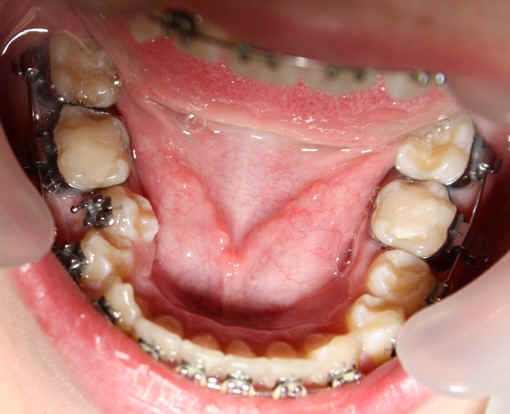

Malpositioned Premolar 13 year-old Caucasian boy

2009/10/31 U .016x.022, L to be .016 Niti